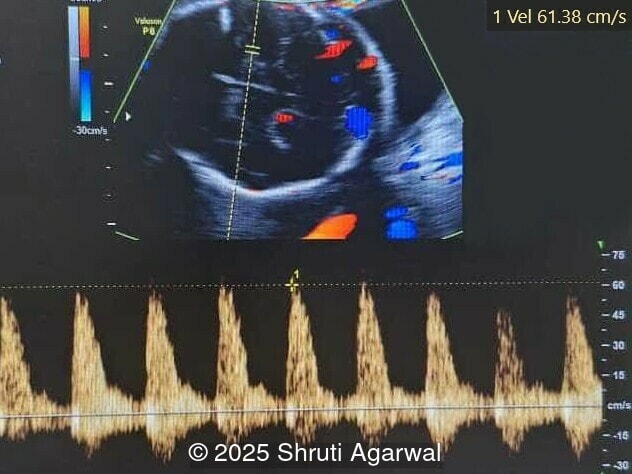

We present a case of fetal anemia due to a giant chorangioma.

• Image 5: normal cardiac inflow

• Image 6,7: Mitral regurgitation

Chorangiomas greater than 5cm are referred to as a giant chorangioma and occur in approximately 1 in 2,700 pregnancies [2]. Giant chorangioma can be clinically significant, causing various fetomaternal complications. In a study reviewing 175 cases of chorangioma, approximately 34% of giant chorangiomas experienced complications [2]. Arteriovenous shunting in giant chorangioma can increase venous return to the fetal heart, causing hypervolemia, tachycardia, and cardiomegaly, leading to heart failure, hydrops fetalis, and fetal demise. Large lesions can also divert nutrients and oxygen from the fetus, manifesting as growth restriction. Placentomegaly occurs due to a hyperdynamic circulation as a result of arteriovenous shunting.  In such cases, fetus may suffer from anemia and thrombocytopenia due to sequestration of red blood cells and platelets by the tumor. Polyhydramnios can occur due to both direct transudation into the amniotic fluid and to fetal polyuria secondary to the hyperdynamic circulation. Additionally, preterm delivery and maternal mirror syndrome with generalized fluid overload and preeclampsia can occur with giant chorangiomas [2,8].

Prenatal diagnosis depends on ultrasound, however, chorangioma can cause an increase in maternal serum alpha-fetoprotein [3]. Ultrasound examination reveals a hypo- or hyperechoic, well-circumscribed mass, which is usually located underneath the chorionic plate near the umbilical cord insertion, and often protrudes into the amniotic cavity. Color Doppler demonstrates large vascular channels around and within the tumor [6,9]. In cases of giant chorangiomas, echocardiography should be performed to assess cardiac function and measure fetal middle cerebral artery peak systolic velocity for diagnosis of fetal anemia. Regular ultrasounds with Doppler studies are used to monitor tumor size, fetal growth, amniotic fluid volume, and signs of fetal anemia or heart failure. The frequency of exams is based on tumor size and associated complications. With small tumors, assessment may occur every 3-4 weeks, whereas in large tumors, the ultrasound scan may be done every 1-2 weeks [3]. These regular assessments can diagnose conditions that require intervention, such as polyhydramnios, hydrops, or hemolytic anemia.